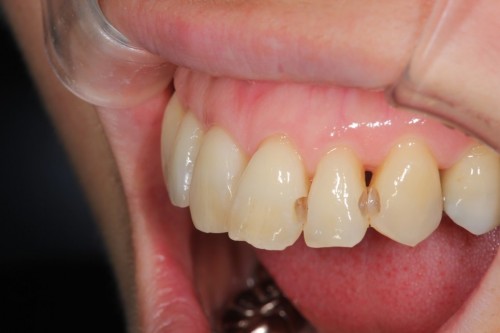

他院で数年前に治療した歯です。白い詰め物がしてありますが、詰め物の奥が虫歯になっております。

白い詰め物と虫歯になった歯のみを取り除きます。通常でしたら型とりを行い、健康な歯まで削って治療する事になります。今回は最小限度しか削ってません。

そしてハイブリッドレジンを詰めました。見た目も噛み心地も問題なく、歯を大きく削る事無く治療を終えました。

ダイレクトボンディング

費用6万円

リスクとして欠ける可能性がある(修復可能)。